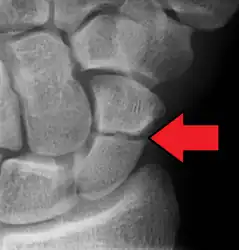

A subtle scaphoid fracture

A more obvious scaphoid fracture on a scaphoid view X ray

Radiolucency around a 12 days old scaphoid fracture that was initially barely visible.[11]

Fracture of the tubercle of the scaphoid bone of the wrist